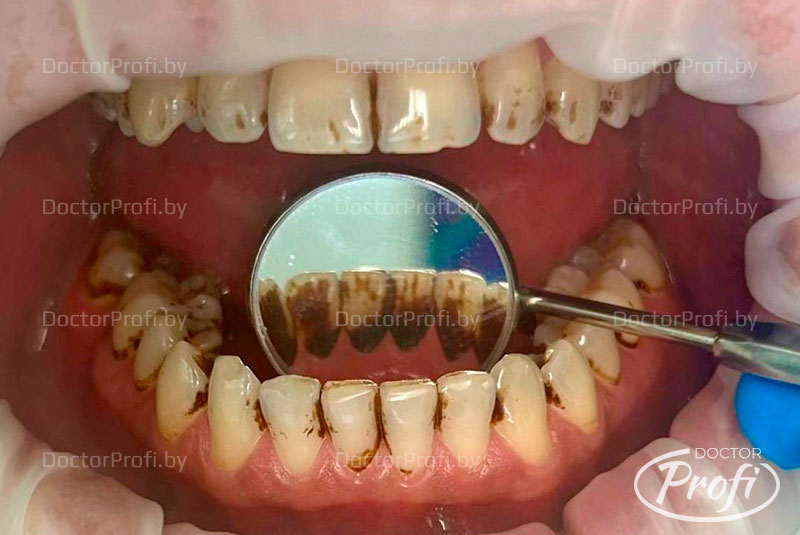

Пациент обратился клинику с желанием сделать профессиональную гигиену полости рта и устранить зубной налет, образовавшийся в результате курения.

- Проведена профессиональная гигиена полости рта с использованием современных методов: ультразвука и технологии Air Flow, что обеспечило бережное и эффективное очищение зубов.

До